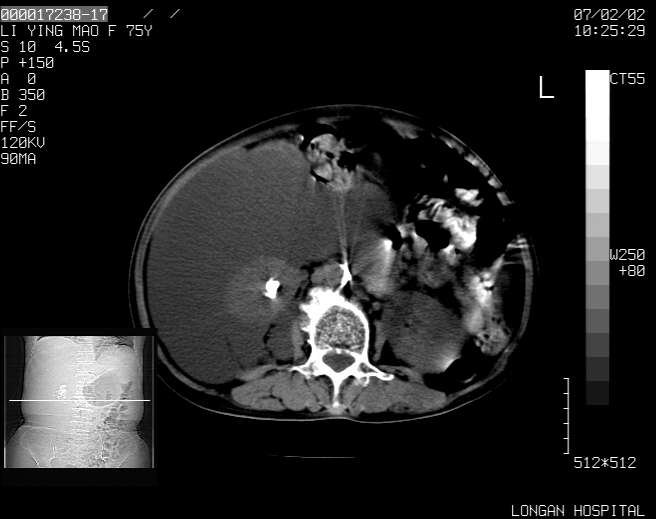

以下是引用dyqct在2007-2-10 8:53:00的发言:[br]考虑:1、肝脏多发囊肿[br] 2、左肾囊肿,右肾多发结石并积水。[br] 3、右胸少量积液。[br] 4、右肾周包裹性积液或淋巴管瘤(有见缝就钻的征象、薄隔、小结节状钙化)?[br] 5、腰椎动脉瘤样骨囊肿?[br] [br] [br]